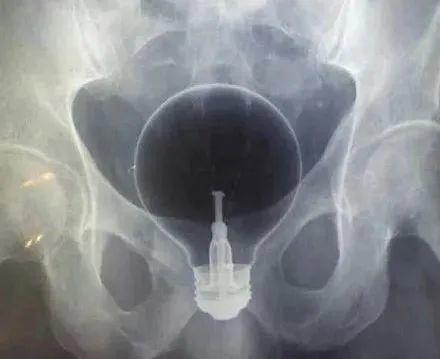

据统计,在急诊室,男性“失物招领”的情况是女性的40倍,大部分都是在直肠中发现的,并且种类繁多:

酒瓶、刀、叉子、喷雾罐、哑铃、灯泡、罗非鱼……只有你想不到的,没有“直男”们不敢塞的,比如说,哑铃。